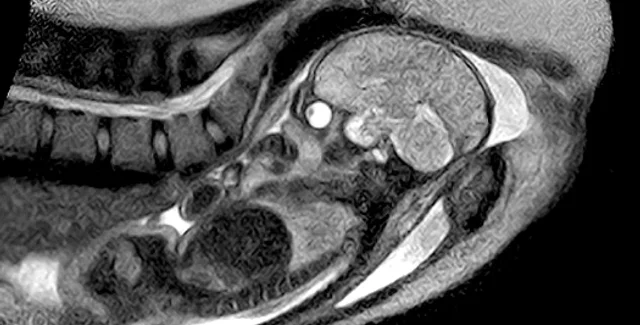

Немецкие медики впервые сняли процесс родов с помощью магнитно-резонансной томографии

Неординарная процедура, проведенная в берлинской больнице Шарите, завершилась успешно. Младенец и мать здоровы и чувствуют себя хорошо.

По словам врача-гинеколога Эрнста Байндера, с помощью полученных изображений можно разглядеть процесс деторождения в деталях - раньше некоторые его особенности приходилось определять буквально на ощупь. В частности, то, насколько необходимо кесарево сечение, если малыш не может выйти из родовых путей. (Сегодня каждая 15-я мама из сотни рожает с помощью кесарева сечения.)